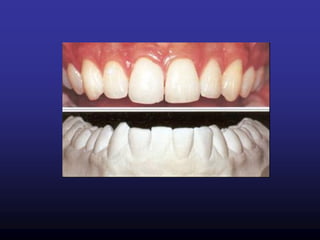

Healthy gingiva

Pale pink & stippled. Narrow

distinguishable free gingival

margin. No bleeding on probing

Mild gingivitis

Localized mild erythema & slight

edema. Some stippling is lost.

Minimal bleeding after probing.

Moderate gingivitis

Obvious erythema & edema.

No stippling, bleeding on

probing

Severe gingivitis

Fiery redness, edematous &

hyperplastic swelling, complete

absence of stippling, bleeding on

probing & spontaneous

hemorrhage.

Mild gingivitis in anterior area:

Mild erythema in maxilla. Slight

edematous swelling & erythema.

In mandible, slight edematous

swelling & erythema.

Papilla Bleeding Index: Grade 1

& 2

Stained plaque: Small plaque

accumulations arounds the necks

of the teeth & in interdental areas.

Moderate gingivitis in

anterior teeth :Erythema

& enlargement of gingiva

pronounced in mand than

in maxilla.

Papilla Bleeding Index :

grade 3 & 4

Stained plaque : Moderate plaque

accumulation in maxilla. Heavier plaque in mandible.

Radiographically, no destruction of interdental bony septa.